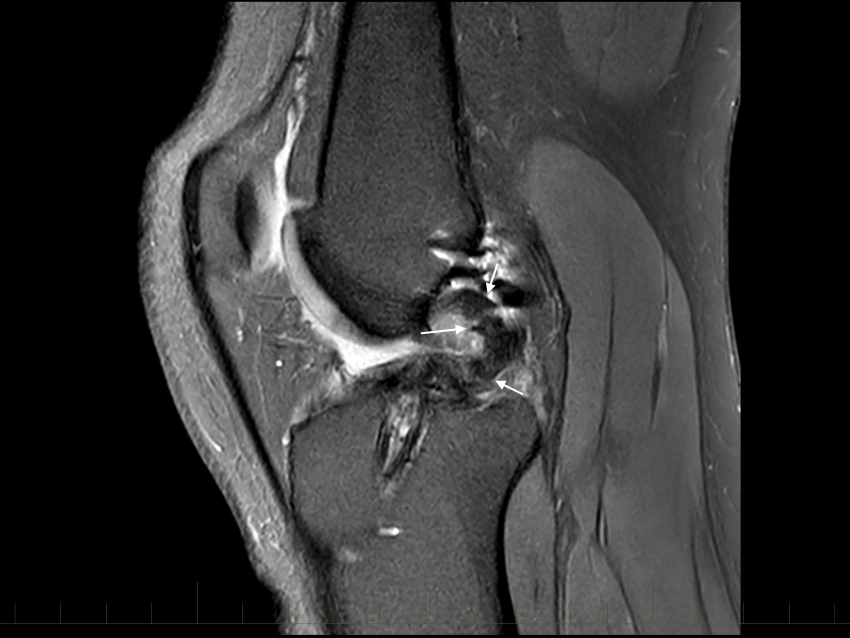

The ACL graft is ruptured with a loss of the normal ACL contour and signal. There is a focal are of full-thickness cartilage loss on the posterior, weight-bearing portion of the lateral femoral condyle. This measure approximately 15 x 10mm. There is also thinning and irregularity of the articular cartilage involving the posterior aspect of the lateral tibial plateau with a small area of full thickness cartilage loss and subchondral reactive change. These chondral changes were not present at the time of her first surgery. There appears to have been trimming of the mid and posterior thirds of both menisci. These meniscal remnants are small and irregular.